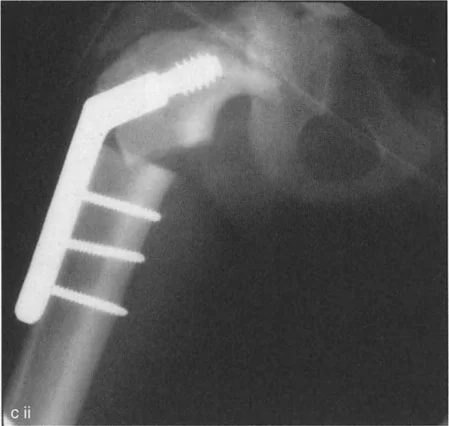

جراحة عظم الفخذ الفحجاء (Valgus Osteotomy) لتصحيح الورك الفحجاء (Varus Deformity)

تُجرى هذه الجراحة عندما يكون عنق الفخذ مائلاً جدًا للأسفل (الورك الفحجاء). تهدف العملية إلى زيادة زاوية عنق الفخذ، مما يجعلها أكثر عمودية.

• إطالة آلية المبعدة: في حالات الورك الفحجاء الخلقي، قد تتطلب إطالة آلية العضلة المبعدة. الأستاذ الدكتور محمد هطيف، في عام 1998، طور إجراءً جديدًا يتضمن إزالة كامل ارتباط العضلة الألوية الوسطى والصغرى بالتواصل مع العضلة رباعية الرؤوس (العضلة المتسعة الوحشية). هذا الإجراء يحرر المدور الكبير من تقلص التبعيد خارج المفصل، مما يسمح بتقريب عظم الفخذ القريب ضمن قيود الارتباطات الكبسولية. كما يتطلب تحرير العضلة الكمثرية التي يمكن أن تحد من الدوران الداخلي والمد والتقريب. يتم إعادة تثبيت الوتر المشترك لهذه الوحدة إلى المدور الكبير بعد تقريب الورك لتصحيح تشوه الورك الفحجاء.

• القيود داخل المفصل: إذا كان تحديد التقريب ناتجًا عن تقلص كبسولي أو التصاقات داخل المفصل، فقد يتطلب الأمر بضع كبسولة (Capsulotomy) لتحقيق التصحيح الكامل. إذا كان السطح المفصلي مشوهًا، فقد لا يمكن تحقيق التصحيح الكامل إلا بعد إعادة تشكيل رأس الفخذ.

• مستويات القطع: يمكن أن يكون القطع فوق المدور الصغير (Intertrochanteric) أو تحته (Subtrochanteric).

• جراحة عظم الفخذ الفحجاء: إذا كان القطع تحت المدور الصغير، فإنه يميل إلى إرخاء وتر العضلة القطنية الحرقفية، مما يسهل التصحيح. إذا كان القطع فوق المدور الصغير، فإنه يشد الوتر، مما قد يجعل الجراحة أكثر صعوبة.

• لذلك، يفضل الأستاذ الدكتور محمد هطيف إجراء جراحة عظم الفخذ الروحاء فوق المدور الصغير، وجراحة عظم الفخذ الفحجاء تحت المدور الصغير، لتحسين النتائج وتسهيل الجراحة.